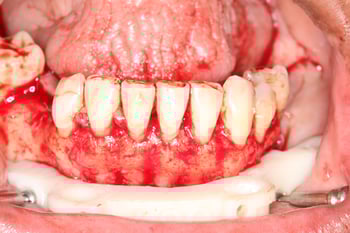

Definitive Mandibular Solution: Conus Overdenture

For the lower arch, we selected a Conus overdenture featuring titanium abutments milled to 5 degrees with precisely fitted gold copings. This friction-fit design provides excellent retention while allowing the patient to remove the prosthesis for hygiene.

The approach delivered an ideal balance of stability, cleansability, and long-term serviceability, making the implant overdenture both functional and patient-friendly.